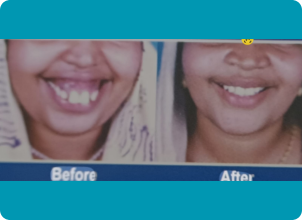

Our Happy Customers

Join thousands of happy patients who trust us for gentle, expert care and beautiful smiles. Your perfect dental experience starts here!

varalakshmy m"I had a good experience about my surgery.I had fear during surgery but now I am feeling so happy because now my facial appearence is more good than earlier. After surgery, most of my friends,relatives and family have the very good opinion. And also he is the wonderful person, he always gives the positive energy. Thank you so much Dr.Philip Mathew sir and the Team."

Sijo Varghese"Orthognathic Surgery was conducted for my daughter by Dr. Philip Mathew. The makeover is really attractive and I should appreciate the Doctor for his aesthetic sense and his endeavour to make people smile with confidence."

Sana Fathima"I had a good experience about my surgery .l had fear during surgery but now l am feeling so happy because now my facial appearance is more good then earlier. After surgery, most of my friends,relatives and family have the very good opinion. Thank you so much Dr.Philip Mathew sir"